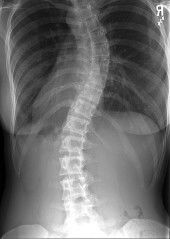

Ibu ada masalah tulang belakang.

Ada tak ibu2 dalam ni ada scoliosis? Ada apa2 effect tk kalau nak bersalin nanti? Kena ceaser atau boleh normal ya.. Please share pengalam an. #firstbaby #37w

saya pun ada minor scoliosis. tak pasti ada kaitan ke tidak, saya beranak czer.